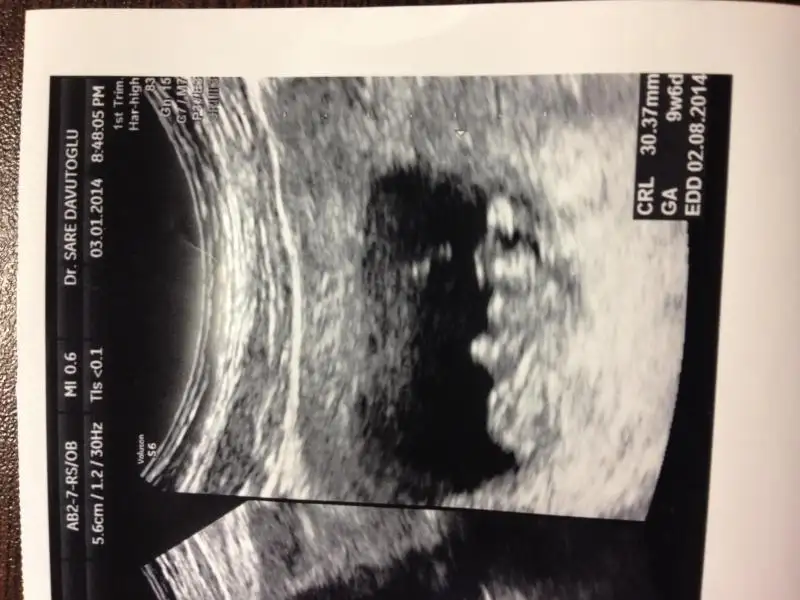

Arkadaşlar benim ilk bebeğim inşallah tüp bebek tedavisi ile oldu.tahmin edersiniz ki her devremiz merakla heyecanla oldu tuttu mu tutmadı mı kese var mı yok mu kalp atışı derken çok şükür hepsinden olumlu ve bizi sevindiren haberler alarak 11. haftamıza gelebildik.10 haftalıkken dr umuz cinsiyeti ile alakalı kesin bişey göremediğinden bilgi vermedi bir sonraki gelişinde dedi ve daha iki haftamız var=(belki siz bişiler dersiniz biraz erken ama merak işte=)